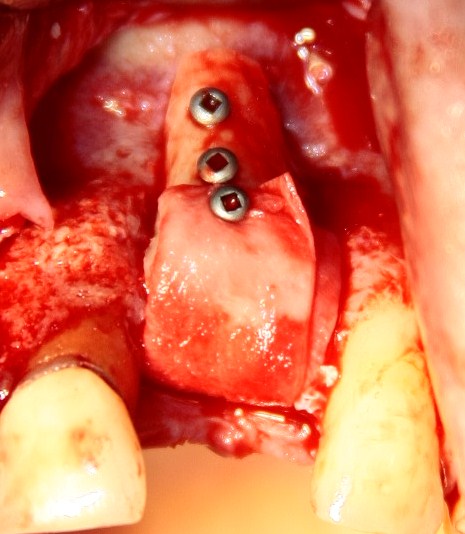

Делаем разрез, скелетируем костную ткань:

Как видите, коллагеновая мембрана полностью резорбировалась, а костный блок прижился и интегрировался на челюстной кости. Можно убрать винты:

и приступить к подготовке лунки под имплантат:

По существующим правилам, при установке импланта в области фронтальной группы зубов, его ось должна выходить на небную поверхность коронки или режущий край. Чего мы и добиваемся, контролируя процесс с помощью пинов.

Я планирую установить имплантат Dentsply Friadent XiVE диаметром 3.8 и длиной 13 мм. Это оптимальный размер импланта для протезирования боковых резцов.

Установка импланта:

Убираем имплантодержатель. Обратите внимание, что полированная фаска вокруг шейки импланта находится над уровнем костной ткани. Чрезмерное погружение импланта — весьма распространенная имплантологическая ошибка.